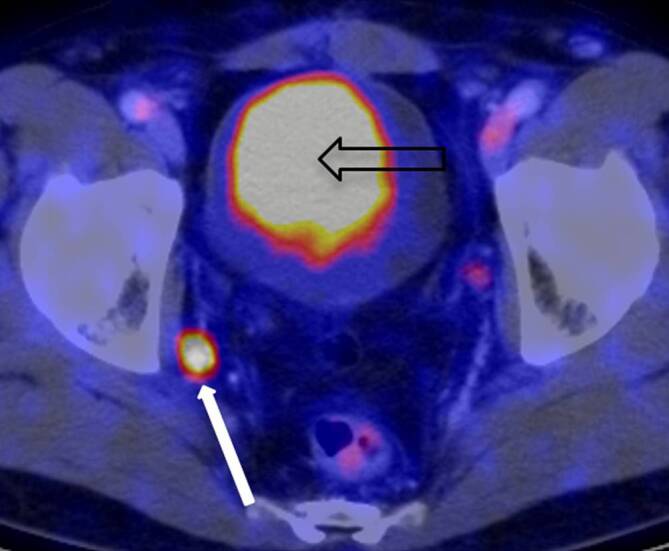

Durch einen als revolutionär zu bezeichnenden Wandel im Auftreten des Prostatakarzinoms hat sich der Stellenwert der Knochenszintigraphie freilich zwischenzeitlich gewandelt von einem Instrument der Erstdiagnose von zuvor klinisch inapparenten Tumoren hin zu einem Verlaufsdiagnostikum insbesondere zur Therapiekontrolle, sie ist und bleibt aber unverzichtbares Hilfsinstrument der uroonkologischen Therapie. So wie die Skelettszintigraphie ab den 1970er-Jahren mehr und mehr die konventionelle Röntgendiagnostik als Diagnostikum der Wahl von ossären Filiae ablöste, ist in den letzten Jahren ein weiterer Erfolg der Nuklearmedizin über die Radiologie zu beobachten: war die Computertomographie des Abdomens, erstmals 1977 im Zusammenhang mit dem Prostatakarzinom in Erscheinung getreten, ab den 1980er-Jahren ein hochwillkommener neuer Routineansatz zur Detektion von viszeralen Metastasen, so wird dieses Verfahren seit gut 10 Jahren – zumindest dort, wo entsprechende Einrichtungen vorgehalten werden – erneut nuklearmedizinisch durch die Etablierung des 68Gallium-PSMA-PET-CT (Abb. 8) bei der Detektion von kleinsten lymphogenen und viszeralen Metastasen ersetzt oder zumindest ergänzt [38, 39]. Die Radiologie ist gleichwohl auch heute noch von großer Bedeutung für die Prostatakarzinomdiagnostik. Wie bereits weiter oben angedeutet seit knapp 10 Jahren zunehmend in Form der Magnetresonanztomographie der Prostata im Rahmen der Primärdiagnostik vor bzw. zur Unterstützung einer gezielten Prostatastanzbiopsie [40].